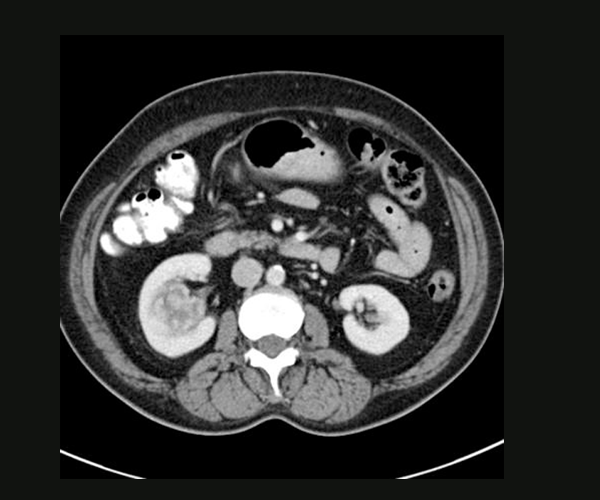

CT IMAGE SHOWING RIGHT RENAL PELVIC

UROTHELIAL CANCER OF RENAL PELVIS /URETER: